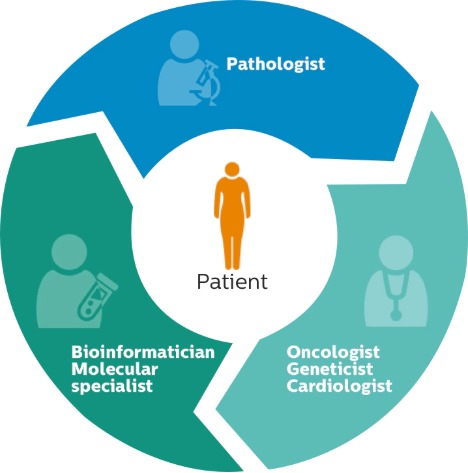

At Philips we put the patient at the center of everything we do.

This patient-centric approach supports precision care.

Digital pathology opens new, innovative ways to help laboratories and hospital systems improve workflows and provide better patient care.